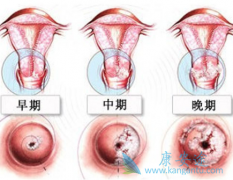

�����ӹ�����Ů����˵�Ƿdz������ģ� �ӹ��� �Ǹ����������Ķ�������֮һ�����ķ�������Ů����ֳ���ٰ�����ռ��λ������ͳ�ƣ�ÿ��Լ20����Ů�����ڹ�������������вŮ�Ե������ͽ����� �����ӹ����������尩���ֳ��ӹ���Ĥ�����������������50��60 ...

�����ӹ��������ļ����Ƿdz������ģ����ߵ��� �ӹ��� ������Щ֢״�أ�����Ů��������˵����Ӧ����ô����Ԥ���أ�������������������;Ϊ��������صĽ��ܡ� ����һ���ӹ���Ĥ����֢״����Щ��1��������������Ѫ���ǹ���������֢״�ϳ�����һ�֣���Ѫ���ɶ� ...